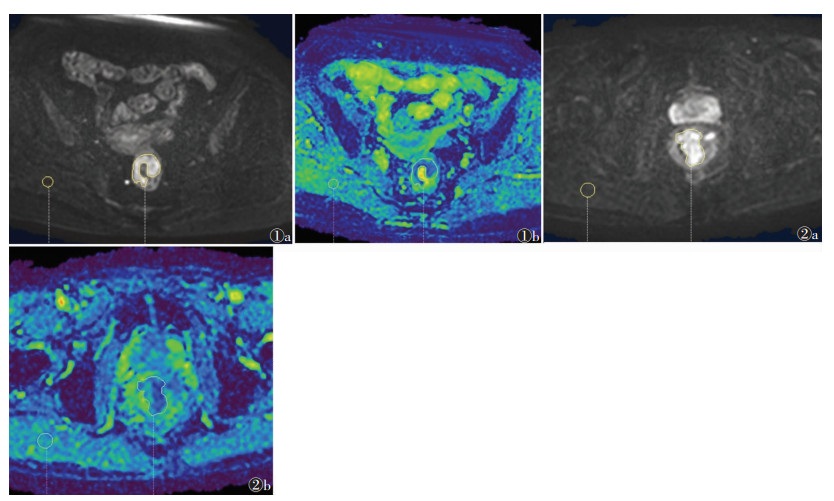

转移淋巴结组ADCmin、ADCmean、rADCmin、rADCmean值均较非转移淋巴结组小,其中ADCmin、rADCmin、rADCmean值差异均有统计学意义(均P<0.05),ADCmean、ADC肌值差异均无统计学意义(均P > 0.05)(图 1,2)。

| 注:图 1患者,女,70岁,中段直肠腺癌,有区域淋巴结转移。图 1a为DWI序列,b=1 000 s/mm2,直肠壁不均匀增厚,呈高信号;图 1b为ADC图,直肠癌病灶ADCmin=0.360×10-3 mm2/s,ADCmean=1.150×10-3 mm2/s,ADC肌=1.430×10-3 mm2/s,rADCmin=0.250,rADCmean=0.800。图 2患者,男,72岁,下段直肠腺癌,无区域淋巴结转移。图 2a为DWI序列,b=1 000 s/mm2,直肠壁不均匀增厚,呈高信号;图 2b为ADC图,直肠癌病灶ADCmin=0.520×10-3 mm2/s,ADCmean=1.160×10-3 mm2/s,ADC肌=1.360×10-3 mm2/s,rADCmin=0.380,rADCmean=0.850 图 1~2 直肠腺癌伴/不伴淋巴结转移的DWI及ADC图像 |